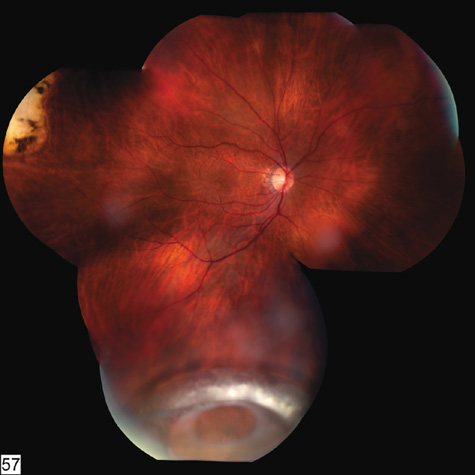

Fig. 11. A: Serous detachment of the macula and intraretinal and vitreous hemorrhage after the eye was struck with a baseball. B: Three months later. The hemorrhages have cleared, revealing severe pigment epithelial necrosis. The visual acuity is counting fingers.

The late manifestations of contrecoup injury to the retinal pigment epithelium (RPE) vary from minor atrophic changes that are seen as transmission defects on fluorescein angiography to massive hyperplasia and migration of the RPE. This later condition results in bone corpuscular and granular pigmentation that resembles retinitis pigmentosa (Fig. 12).71,72 The traumatic pigmentary changes may be confined to the posterior pole, to the periphery, or to certain quadrants, or they may be more widespread. When the trauma to the RPE destroys photoreceptor cells, localized visual field defects result. Arcuate field defects are not found because the overlying nerve fiber nearly always remains intact.

Fig. 12. A: Peripheral pseudoretinitis pigmentosa after blunt trauma, with marked bone spicule formation and atrophy of the nasal retinal blood vessels. B: The disc and macula of the same eye have normal blood vessels. The other eye is normal.